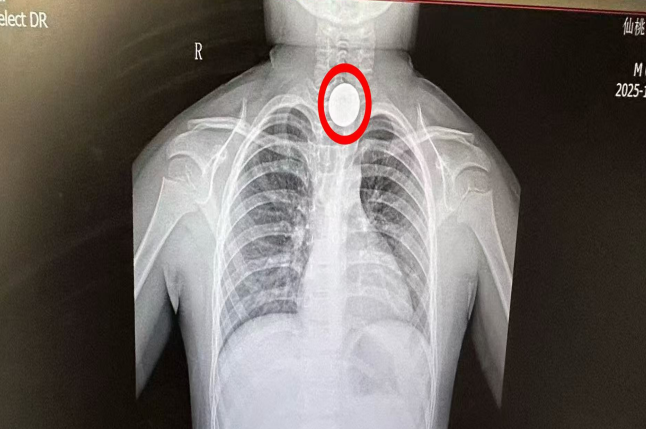

“硬币一拿出来,孩子马上就笑了,还能跟我们合影!”近日,6岁男童小宇(化名)在仙桃市第一人民医院耳鼻咽喉科顺利康复。约一小时前,他不慎吞下的一枚一元硬币,被医生用导尿管微创技术巧妙取出,全程安全无创,孩子未受痛苦。

此前,小宇因误吞硬币后出现吞咽困难,被家长紧急送至市一医。胸部DR检查显示,一枚圆形金属异物嵌顿于食道上段,如不及时处理,存在黏膜损伤、食道穿孔甚至引发窒息的风险。接诊的耳鼻咽喉科周宏医师果断决定采用“双腔导尿管食管异物取出法”(Foley管法)进行处理。该方法无需全麻,创伤极小,但对医生操作技巧与患儿配合度要求较高。